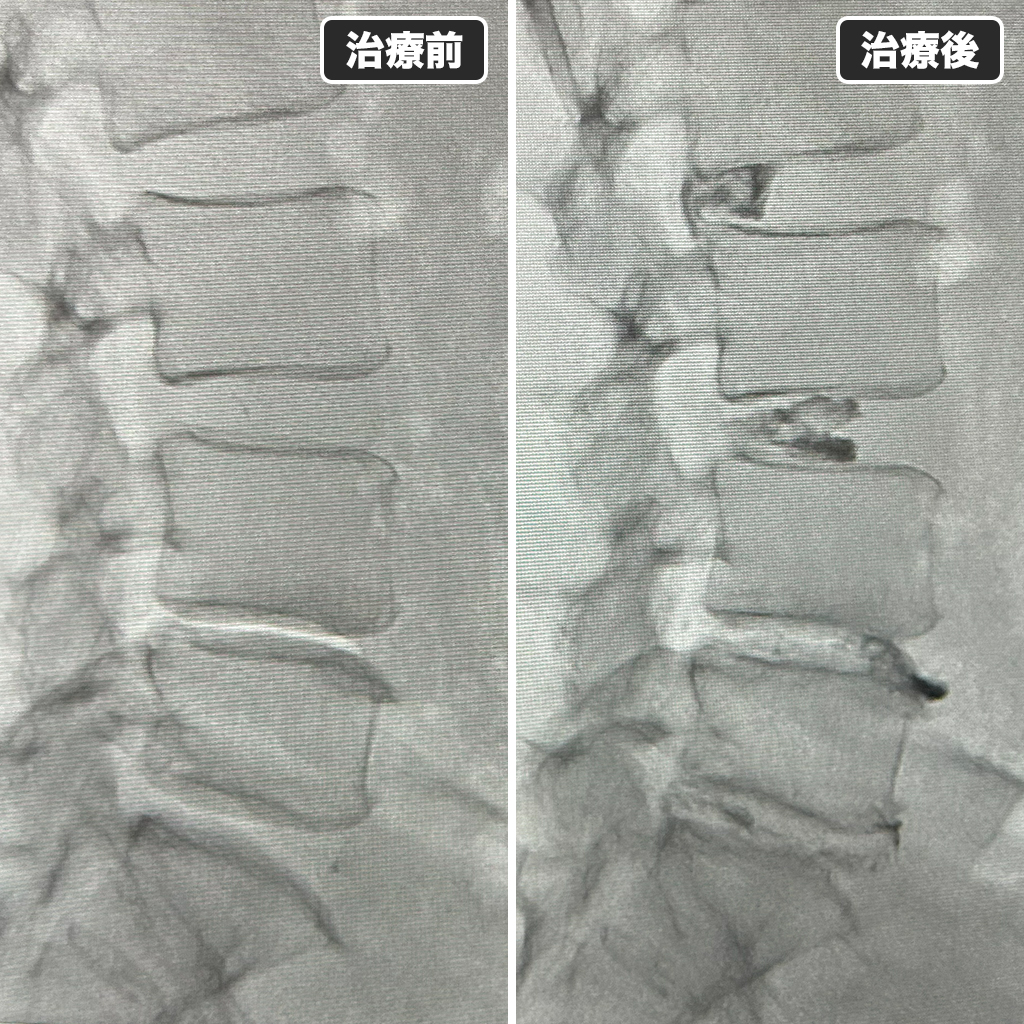

治療前後のレントゲン

治療前後のレントゲン写真になります。左側が治療前、右側が治療後になります。